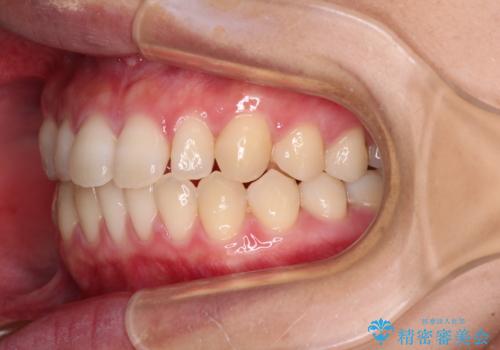

空隙歯列(すきっ歯)は、舌の突出癖をある程度改善できたとしても、後戻りにより隙間が開きやすいと言われています。

裏側から細いワイヤーで保定するとともに、睡眠時のマウスピース装着を徹底していただくことで、後戻りを最小限にとどめます。